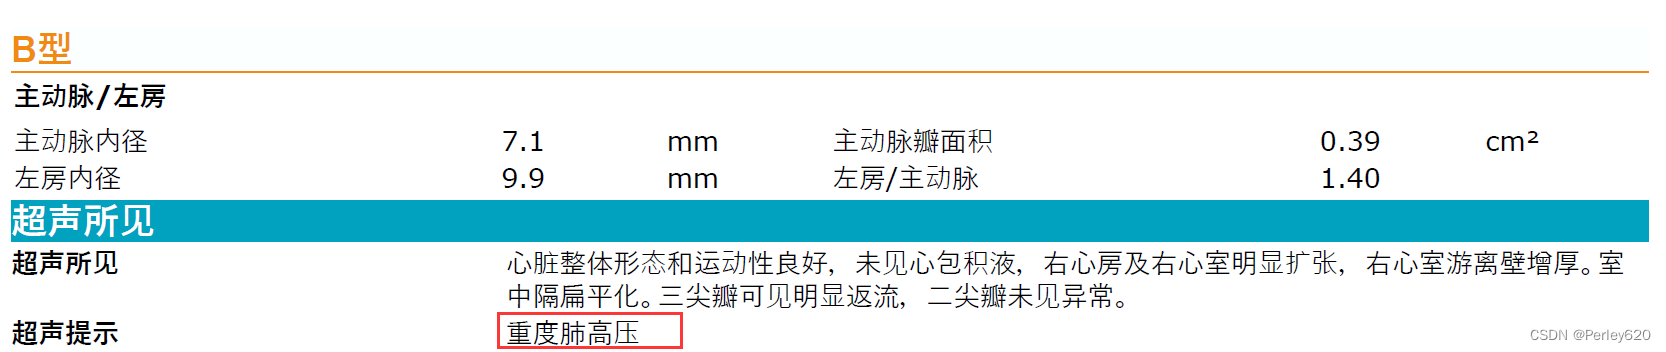

然后给她拍X光片,给她做彩超看心脏,宠物医院的院长看了半天,也没能确定是什么问题,她觉得是心脏左心室隔膜缺损,但没法给定论。

我们就去了宠物医院的总院,找了总院的院长做进一步的检查,最终是重度肺高压,就是很严重的一种病。

诊断的B超图